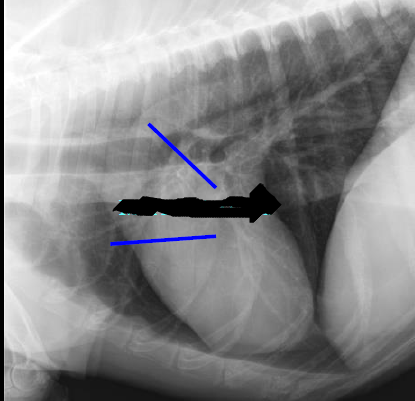

Cardiac silhouette

Caudal mediastinal reflection

Caudal mediastinum

Caudal vena cava

Cranial mediastinum

Cranioventral mediastinal reflection

Descending aorta